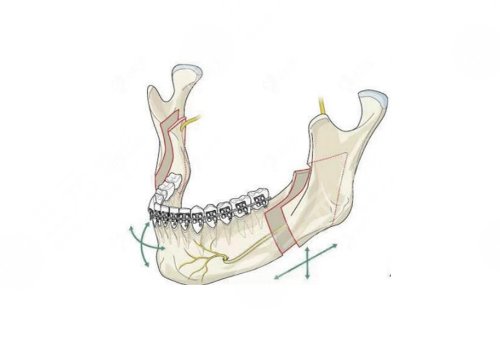

尹宏宇:副主任医师,毕业于清华大学医学部北京协和医学院整形外科学博士,临床经验丰富,工作当中稳扎稳打,会不断提升自身的专业水平,拥有着临床及口腔双重行医资格急诊型外科和口腔颌面外科双重专业技术资格。擅长各类整形美容手术及牙颌面畸形整复,尤其是在正颌手术方面的临床经验充足,对面部的骨骼结构了然于心,能够通过精湛的技术和前沿的审美重塑面部骨骼的外观以及口腔内的咬合功能。

面诊过程当中医生很详细的对我的面部进行了检查,通过x光片了解了我的骨骼情况,并且为我讲解了整个手术的操作过程以及手术后会存在的一些风险,听医生说完之后心中既期待又紧张,看到医生的专业水平很高,所以当即就决定预约手术。